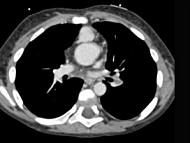

问题 患者,男性,8岁,发绀、气促,易感冒,彩超提示只见一个心室,CT检查如图所示,请选择正确的选项 ( )

选项 A、最常并发肺动脉瓣及瓣下畸形 B、可伴有内脏心房异位、房间隔缺损、共同心房、双上腔静脉等发育畸形 C、为一种较为复杂的先天性疾病 D、以前诊断主要依靠心血管造影 E、考虑为单心室共同动脉干

答案 ABCDE